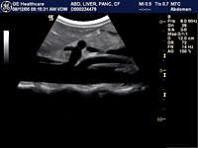

图中所显示图像中分出后下走行的分支为?(?)A.肾动脉B.腹腔动脉C.脾动脉D.肠系膜上动脉E.腹主动脉

问题 图中所显示图像中分出后下走行的分支为?(?)

选项 A.肾动脉 B.腹腔动脉 C.脾动脉 D.肠系膜上动脉 E.腹主动脉

答案 D